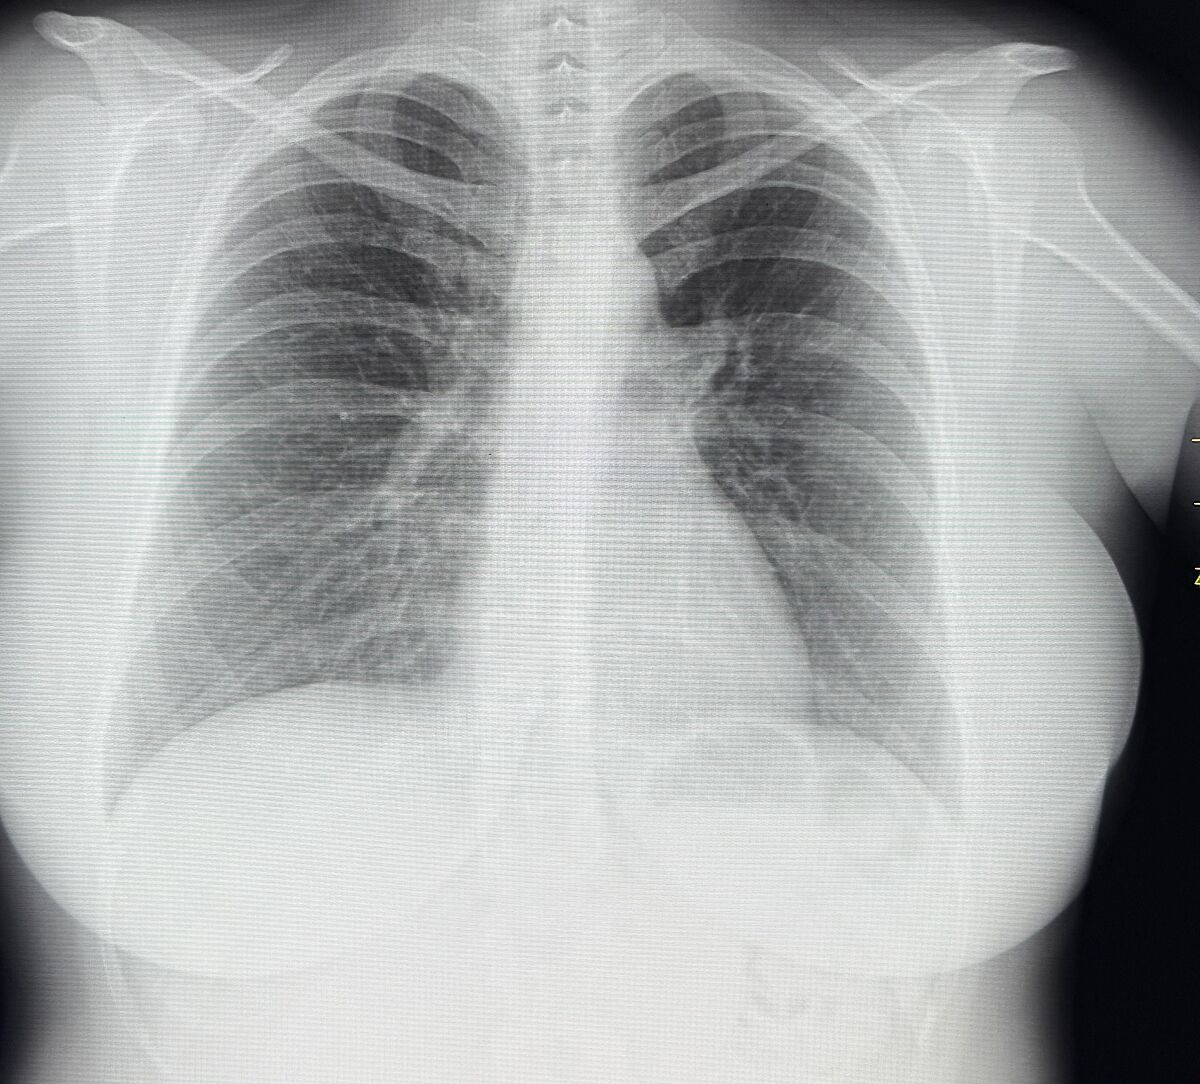

Рентген легенів. Хто розуміється?

Зробила рентген легенів сказали про якісь спайки я не розуміюсь

Де там є спайки?

Це значить, що та частинка легень не працює, бо там шрам. У нас у всіх є ’шрами’ на легенях та на інших органах після хвороб. Це не страшно, якщо органи і далі продовжують виконувати свою функцію. Це як зі шкірою, якщо тільки з´явилися розтяжки на них можна ще вплинути, якщо давно, то вже нічого не зробиш.

Спайки типа рубцов.видно там было воспаление когда-то. Лёгкие там особо не работают. У меня и фиброз и спайки, особо не страдаю. Отдышка может быть, если физ нагрузка.

Слушайте, а у вас позвоночник дугой.